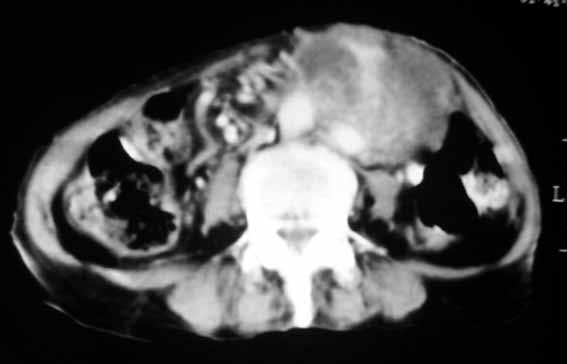

以下是引用余辉在2007-4-30 18:01:00的发言:[br]病灶前方的条状增强影是什么?若是胰腺,位置似乎有点低,若是十二指肠,似乎又不诫该是那样强化,姑且将其看作胰腺吧,那么考虑来源于胰腺粘液囊腺瘤可能性大,其次考虑来源于肠系膜或者后腹膜的肿瘤如平滑肌肉瘤,异位嗜铬细胞瘤及淋巴瘤等。